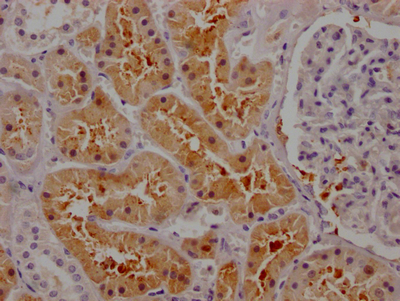

IHC image of CSB-RA261140A0HU diluted at 1:100 and staining in paraffin-embedded human kidney tissue performed on a Leica BondTM system. After dewaxing and hydration, antigen retrieval was mediated by high pressure in a citrate buffer (pH 6.0). Section was blocked with 10% normal goat serum 30min at RT. Then primary antibody (1% BSA) was incubated at 4℃ overnight. The primary is detected by a Goat anti-rabbit IgG polymer labeled by HRP and visualized using 0.05% DAB.